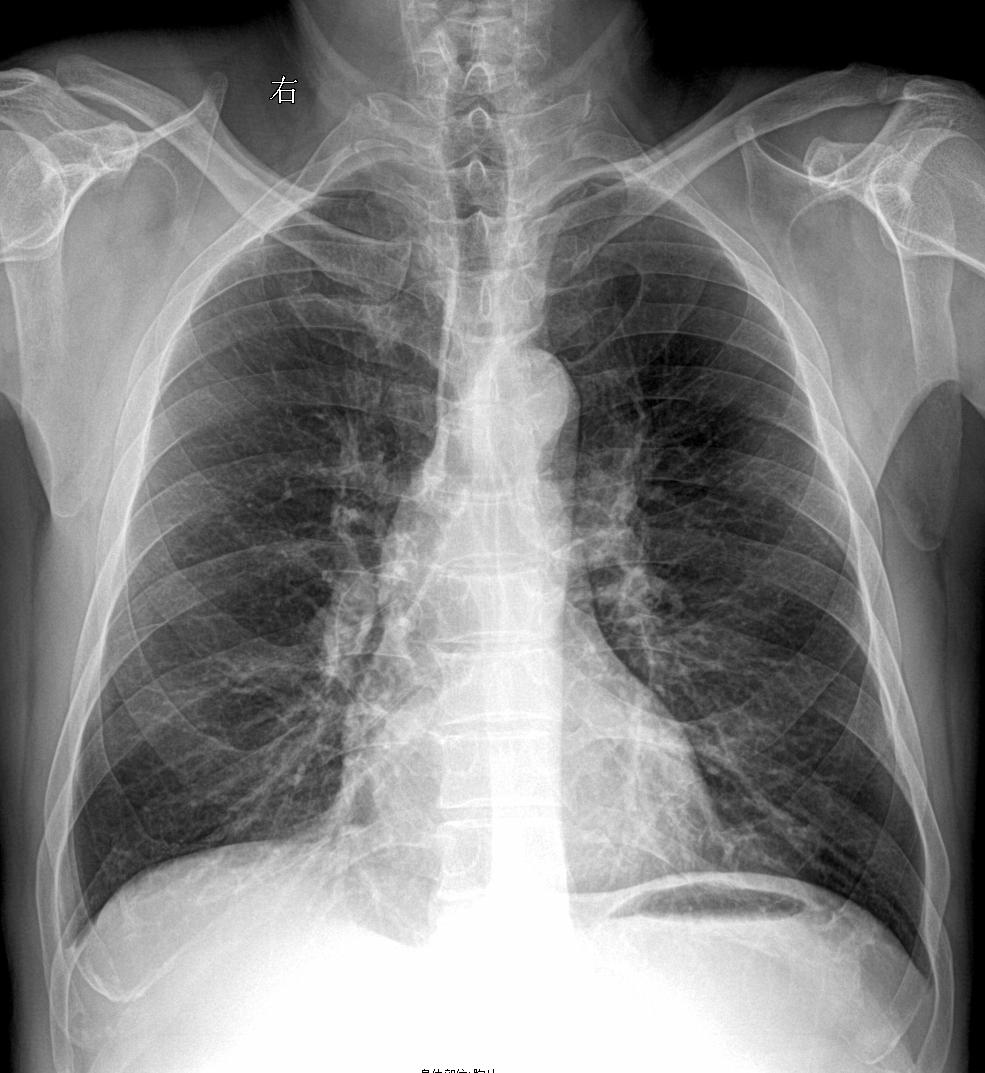

男 57y 咳嗽带红色痰 感冒胸闷就诊

上期被查封 重新发一下家人们 再来一起探讨下肺结核 胸部正位片

2024-06-03 19:23

咳嗽胸闷就诊

2024-06-03 19:30

又来一张,患者主诉:胸闷,咳痰

2024-06-03 19:31

胸闷咳嗽就诊,考虑什么家人们?

2024-05-25 11:15